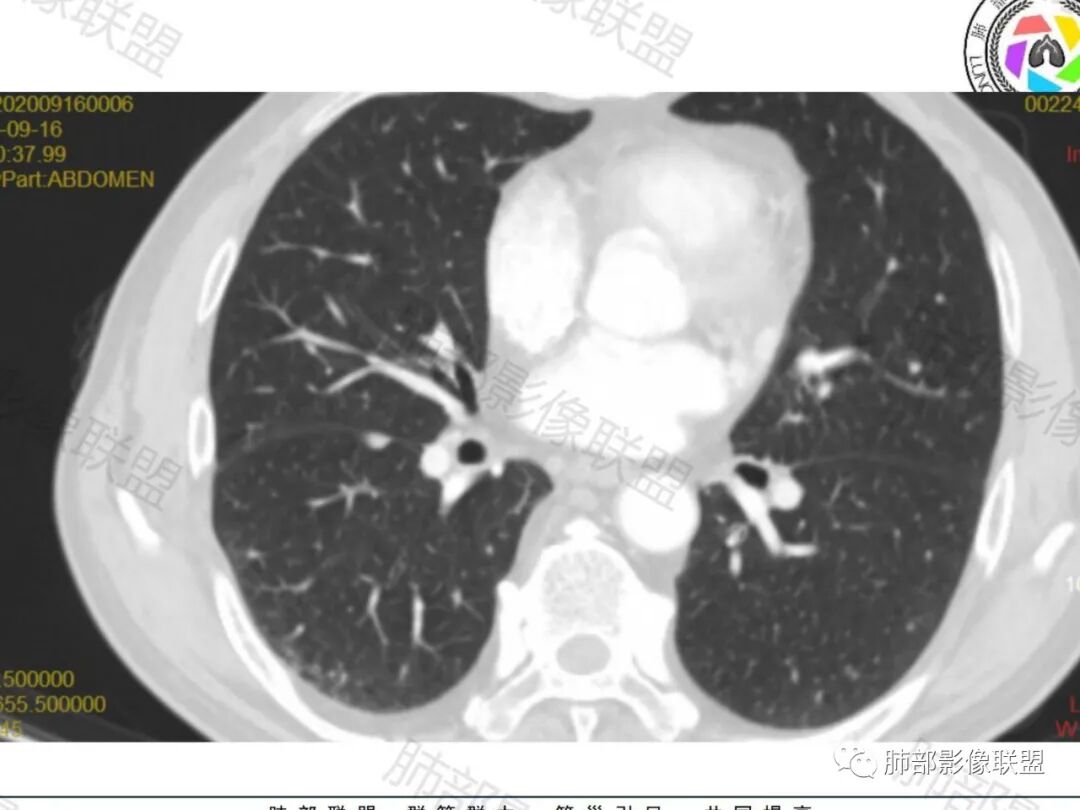

老年人,偶然发现,右肺下叶类圆形软组织占位,密度较均匀,病灶边缘光滑,无毛刺分叶,支气管血管受挤压向外移位,增强病灶强化较均匀。考虑恶性肿瘤,外向内生长,肉瘤,肉瘤样癌,癌肉瘤,其次神经内分泌癌。

老年男性,右肺下叶肿块,边缘光整,血管贴边,部分血管进入,整体强化尚均匀,考虑大细胞癌,鉴别PSP、SFT

右肺下叶类圆形软组织肿块,病灶边缘光滑,无明显毛刺分叶,支气管受压推移,血管贴边,部分血管进入病灶,增强病灶强化不均匀,内可见低密度,病灶与右侧膈肌分界不清,考虑神经内分泌肿瘤,大细胞癌。鉴别PSP

右肺下叶大肿块,血管贴边,部分小分支进入肿块内,密度略欠均匀,边缘总体光滑,支气管关系不明确,老年人,总体考虑恶性,nse高,首先考虑神经内分泌癌,鉴别肉瘤,转移瘤

老年男性,NSE高。右肺下叶软组织肿块,平扫密度均匀,增强后不均匀强化,其内似可见小血管影。肿块边缘光滑,无分叶无毛刺,血管和支气管贴边。考虑神经内分泌肿瘤,鉴别:psp

老年男性,右肺下叶肿块,边界光滑,血管贴边,部分小分支进入,肿块内可见增粗血管,肿瘤指标偏高,总体考虑恶性,不典型类癌?大细胞癌?鉴别PSP。

胸部CT:右肺下叶一类圆形肿块影,边界清楚,大部分边缘光滑、外缘边界模糊,邻近支气管推移、血管贴边,病灶内可见分枝状血管,平扫密度尚均匀,增强后大部分均匀延迟强化,部分与膈肌黏连、尾征?考虑:类Ca>PSP>SFT。鉴别肉瘤样Ca,CD等。